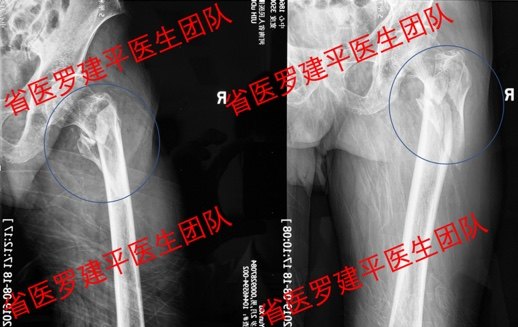

老年髋部骨折常见的有两种:一种是股骨颈骨折,一种是股骨转子间骨折或粗隆间骨折。随着寿命的延长,骨质开始变得疏松,肌肉开始萎缩,特别是绝经期后的妇女,情况更加严重。

国内外大量的研究表明,老年人髋部骨折,如果身体状况允许,无论多大年纪,都应尽早手术,然后积极康复。在我们科,每年都会救治大量的老年髋部骨折,年龄最大的93岁,经过手术治疗、术后功能锻炼,目前恢复良好,患者十分满意。